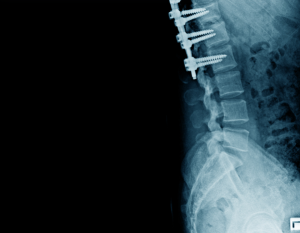

Lateral view of structure bone with internal fixation